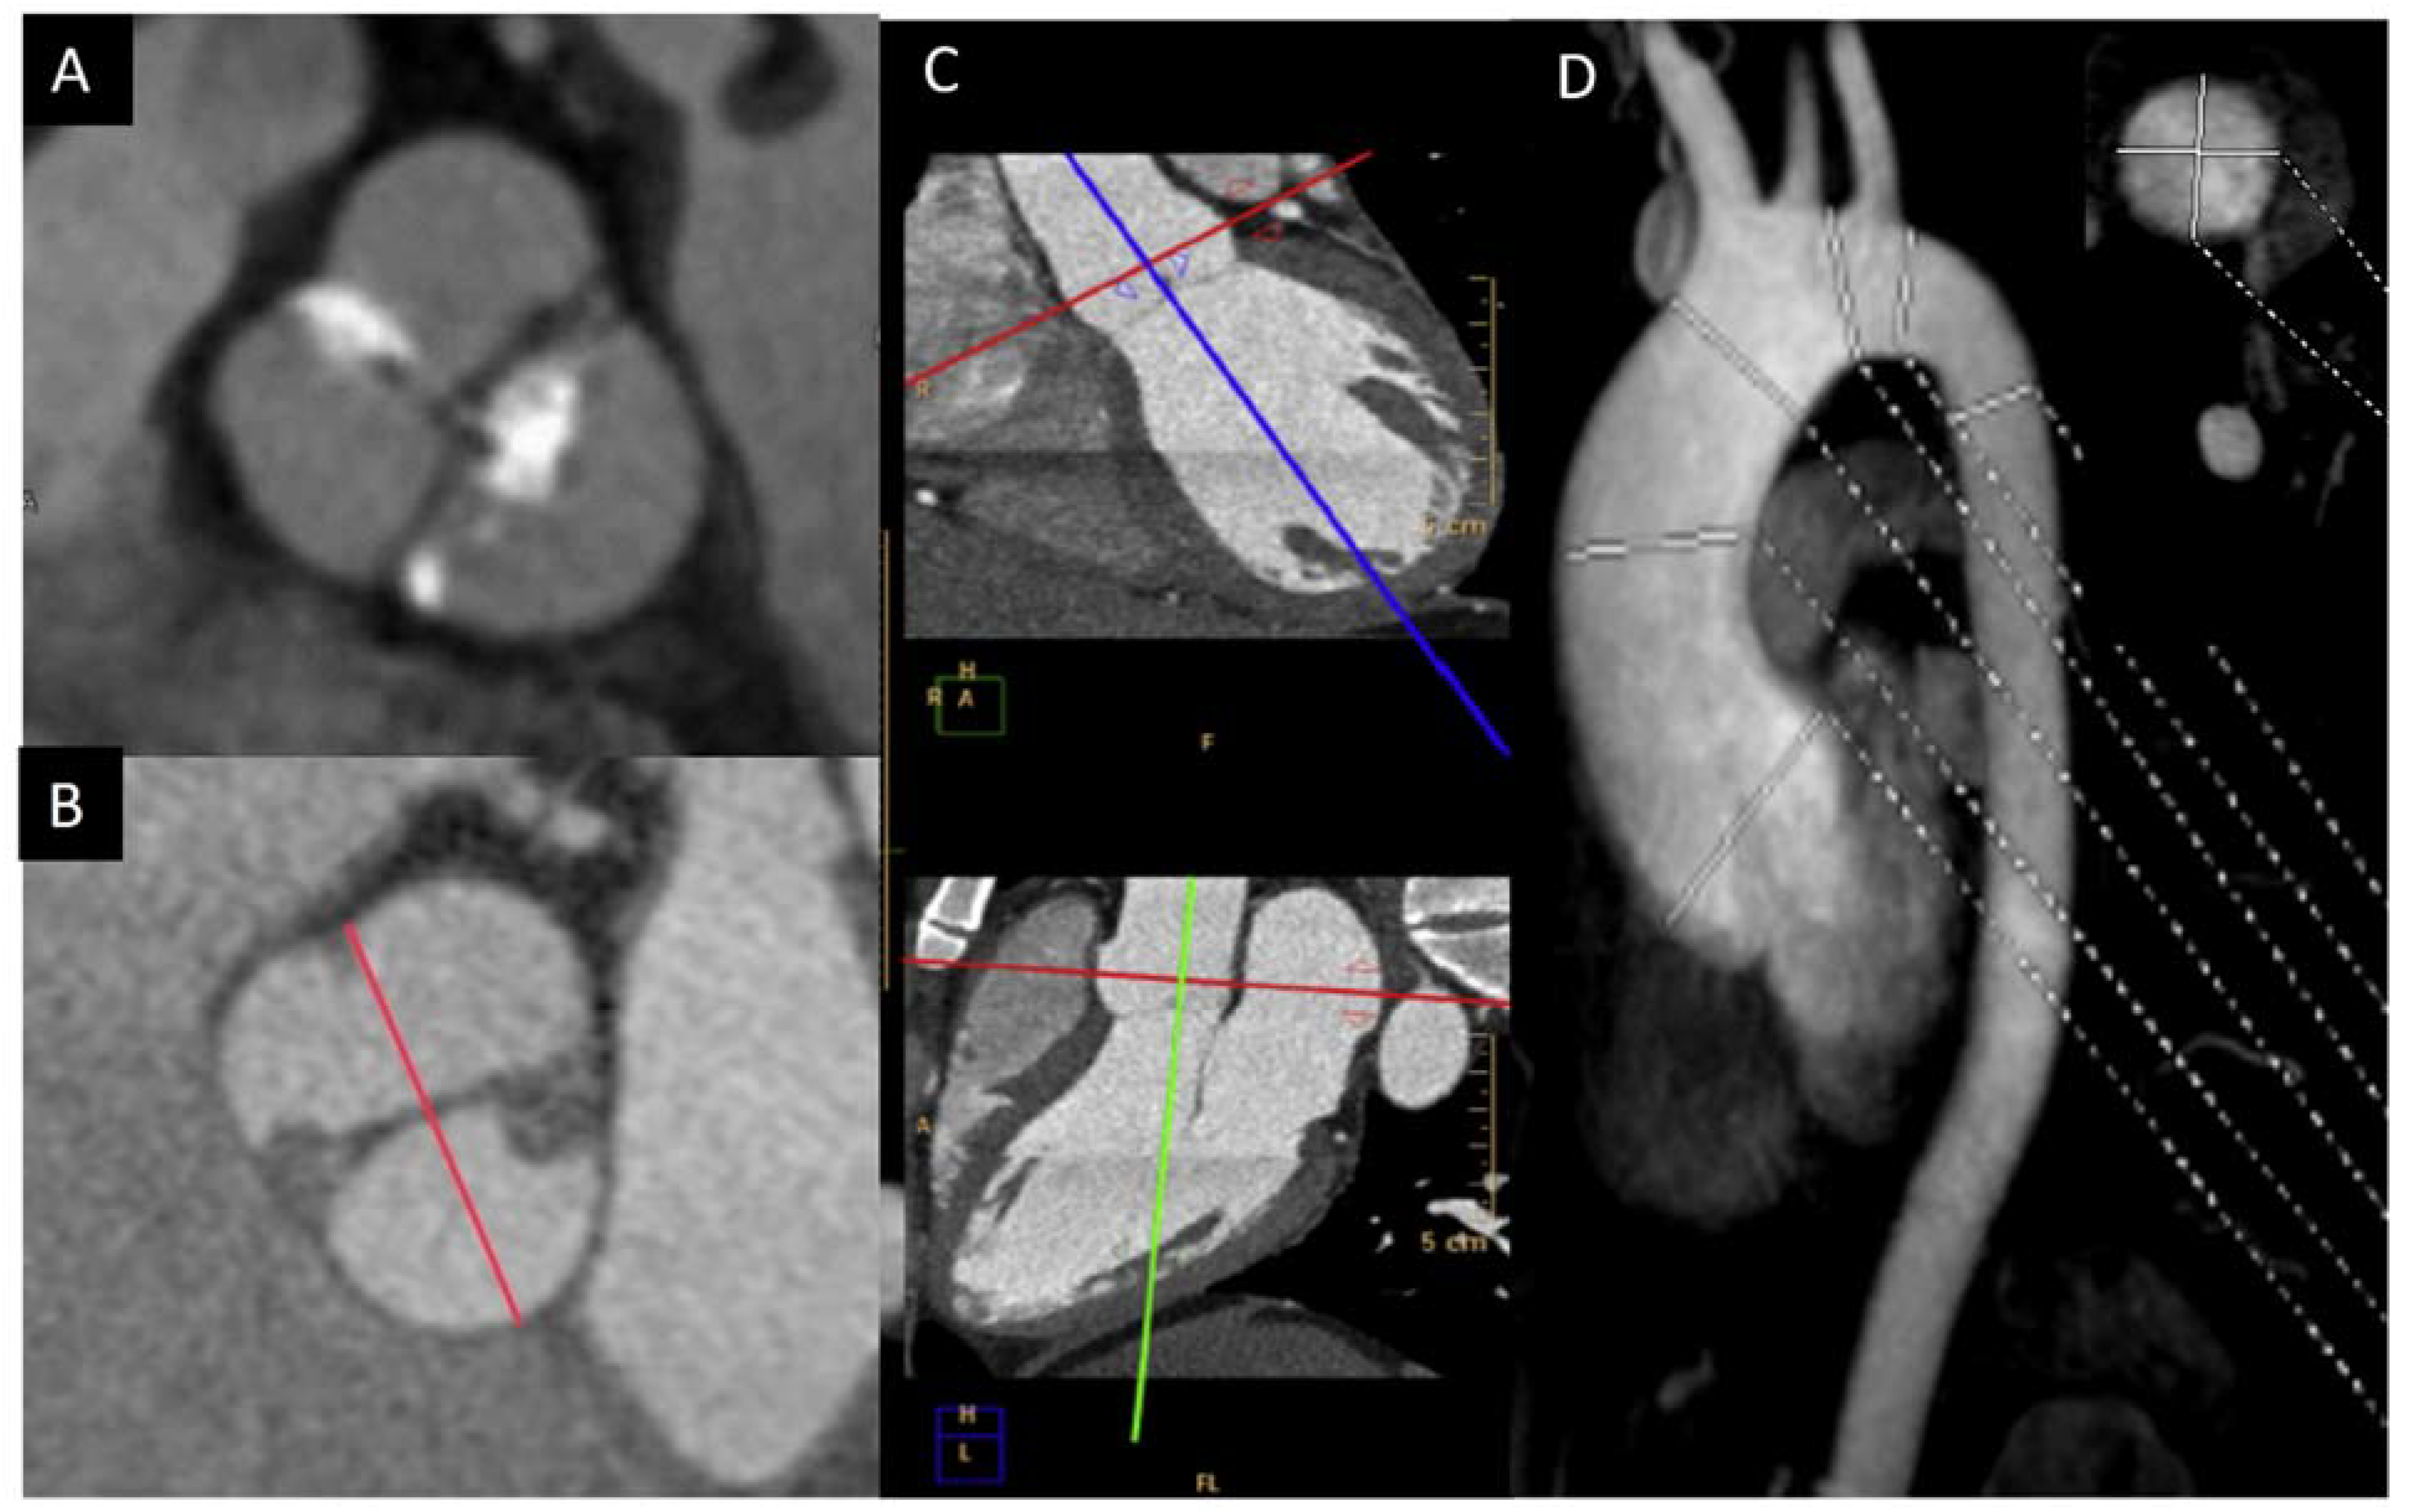

In order to solve the limitations of the TTE, CMR and CT are very useful in the morphologic valve evaluation when it is heavily calcified, and can readily assess aorta diameters [23]. CT can quantify the valve calcification, which can help clinicians to evaluate valve stenosis severity. The multiplanar reconstructions permit CMR and CT to precisely assess the aortic diameters [24,25]. Although CT offers a higher spatial resolution, CMR provides information of the valvular dysfunction and left ventricular function. Cine images (SSFP sequences) can be used for measuring the luminogram of the aorta, particularly in the aortic root, owing the valvular plane movement. Aorta diameters should be measured in double oblique technique) [26] (Figure 3). Screening for coarctation should be performed in BAV patients, however CMR on the first echo is the preferred technique in younger patients in order to avoid radiation.

Figure 3.

BAV by CT showing left−right fusion with raphe calcification and mild non-coronary sigmoid edge calcification (A); CMR showing two-sinus anteroposterior BAV (B); double obliquity image for measuring the maximum diameter of the aortic root by CT (C); thoracic aorta diameters by angio-CMR sagittal projection; the right upper part shows the aortic root section obtained with double obliquity image (D).